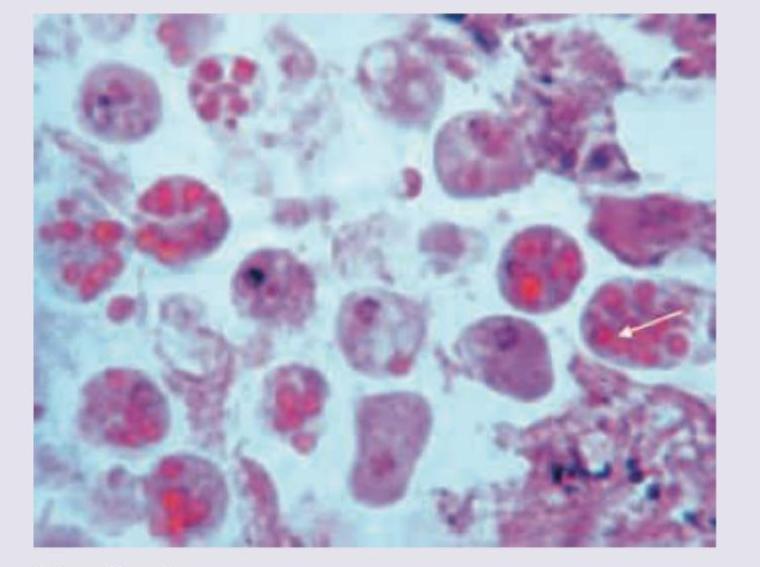

The given inclusion bodies are characteristic of which of the following organisms?

Explanation: ***Cytomegalovirus*** - The image displays cells with marked enlargement (**cytomegaly**) and large, basophilic intranuclear inclusion bodies surrounded by a clear halo, which is the classic **"owl's eye"** appearance pathognomonic for Cytomegalovirus (CMV) infection [1]. - These inclusions are composed of viral particles and are typically seen in various tissues, such as the lungs, kidneys, and gastrointestinal tract, especially in **immunocompromised** patients [1]. *Human papillomavirus* - HPV infection is histologically characterized by **koilocytes**, which are squamous epithelial cells with a non-staining perinuclear halo and a wrinkled, hyperchromatic nucleus. - These changes are typically seen in cervical smears (Pap smears) or skin warts and are distinct from the large intranuclear inclusions of CMV. *Epstein-Barr virus* - EBV infection, particularly in infectious mononucleosis, is identified by the presence of **atypical lymphocytes** (Downey cells) in the peripheral blood, which have abundant cytoplasm and indented nuclei. - EBV does not produce the characteristic "owl's eye" intranuclear inclusions seen in the provided image. *Herpes simplex virus* - HSV infection is characterized by **multinucleated giant cells** with molded nuclei and eosinophilic intranuclear inclusions known as **Cowdry type A bodies**. - While both are herpesviruses, the inclusions in HSV typically give a **"ground-glass"** appearance to the nucleus, which is different from the distinct, haloed "owl's eye" inclusion of CMV. **References:** [1] Kumar V, Abbas AK, et al.. Robbins and Cotran Pathologic Basis of Disease. 9th ed. Infectious Diseases, pp. 367-368.